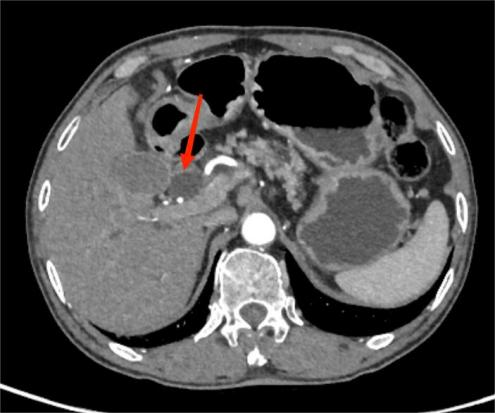

典型病例1:

男,70岁,间断性右腹部疼痛2年,为隐痛,发作无规律,加重1月余。图A:平扫CT示胰腺钩突部团块状稍低密度影,边界不清。图B:增强扫描示病灶呈弱强化。